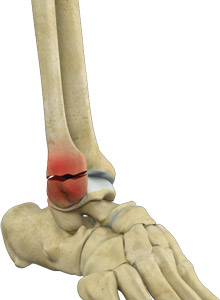

The ankle joint is composed of three bones: the tibia, fibula, and talus which are articulated together. The ends of the fibula and tibia (lower leg bones) form the inner and outer malleolus, which are the bony protrusions of the ankle joint that you can feel and see on either side of the ankle. The joint is protected by a fibrous membrane called a joint capsule, and filled with synovial fluid to enable smooth movement.

Ankle injuries are very common in athletes and in people performing physical work, often resulting in severe pain and impaired mobility. Pain after ankle injuries can either be from a torn ligament and is called ankle sprain or from a broken bone which is called ankle fracture. Ankle fracture is a painful condition where there is a break in one or more bones forming the ankle joint. The ankle joint is stabilized by different ligaments and other soft tissues, which may also be injured during an ankle fracture.

- Medial Malleolus fracture in which the medial malleolus, the inner part of the ankle, is fractured.